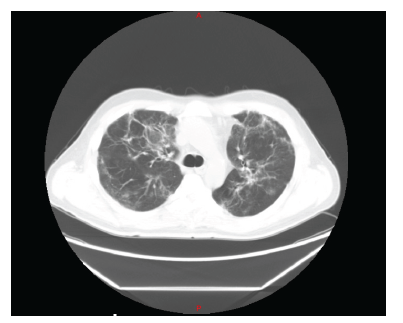

The patient is a 44-year-old male, residing in Colombia, who was admitted to the emergency room on November 24, 2020. His illness started on November 15, 2020, due to fever of 38-39 degrees Celsius, dry cough, anosmia. He presented positive PCR test for SARS CoV2 on November 17. During the first 4 days, he manifested intermittent episodes of dyspnea and chest pain, so he decided to go to the emergency room, where the diagnosis of atypical viral pneumonia was confirmed. Initially, oxygen saturation and inflammatory markers were normal, and it was suggested to continue treatment at home. On November 24, he was readmitted due to worsening symptoms presenting desaturation and dyspnea on exertion. His chest CT scan on admission showed a mixed pattern with ground-glass infiltrates and bilateral diffuse alveolar consolidation (figure 1).